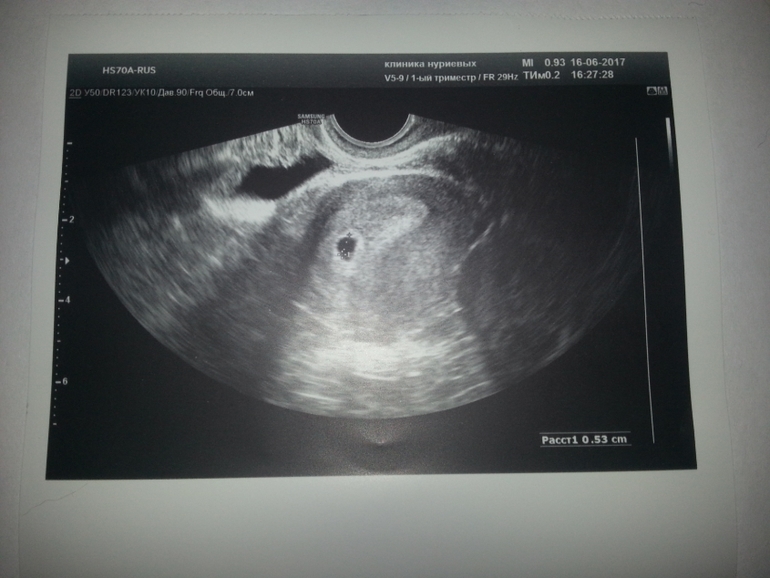

Девочки привет!!! Сделала сегодня у з и , нас нашли!!! Последние м были 11.05,а овуляция по моим подсчетам 26-27.Что-то я думала,что срок побольше,чем врач поставила.Очень рады мы! Тестик и у з и прилагаю!

Поздравляю вас! Увидела УЗИ и сразу узнала Клинику Нуриевых)) поняла,что кто-то из Татарстана значит))